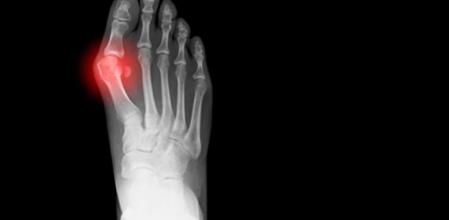

Afectan sobre todo a la inflamación de las articulaciones. Entre otras muchas pueden destacarse la artritis (bajo este concepto también se engloban más enfermedades específicas como la artritis reumatoide, la artritis idiopática juvenil y la artritis psoriásica), la espondilitis, la gota, el lupus y otras enfermedades del colágeno.

Se produce un envejecimiento de la articulación, un desgaste, como en la enfermedad de Paget, la artrosis o la osteoporosis.